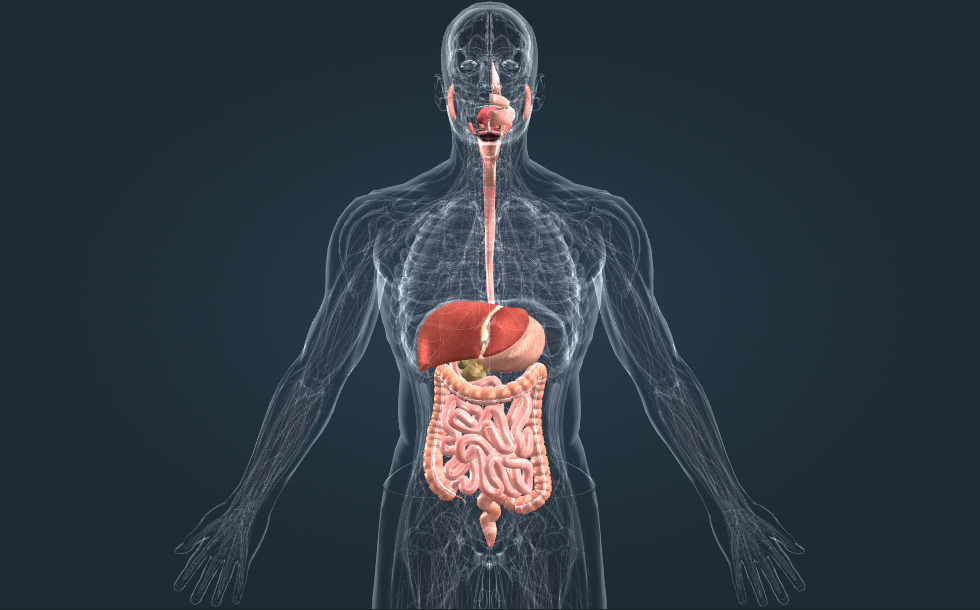

Hệ tiêu hóa

- dạ dày - Protein được tiêu hóa tại cơ quan này. Dịch vị có tính axit mạnh.

- ruột non - Protein, carbohydrat và lipit được tiêu hóa tại cơ quan này. Các chất dinh dưỡng sau khi tiêu hóa sẽ được hấp thụ ở đây.

- đại tràng (ruột già) - Nước và các khoáng chất được tiêu hóa ở đây. Hệ vi khuẩn của nó tạo ra vitamin K và vitamin B.

- trực tràng (ruột thẳng)

- gan - Nó đóng vai trò quan trọng trong việc giải độc và sản xuất mật, giúp tiêu hóa lipit.

- tụy - Nó sản xuất dịch tụy, giúp tiêu hóa lipit, carbohydrat và protein trong ruột non. Nó cũng tiết ra hormone insulin, có tác dụng làm giảm nồng độ đường huyết.

- thực quản

- khoang miệng

- túi mật - Cơ quan rỗng, hình quả lê là nơi lưu trữ mật. Trong khi được lưu trữ tại đây, mật trở nên cô đặc.

Hệ tiêu hóa có vai trò tiêu hóa và hấp thu các chất dinh dưỡng.

Tại miệng, thức ăn được nghiền nhỏ; quá trình tiêu hóa carbohydrat cũng bắt đầu tại đây. Protein được tiêu hóa trong dạ dày, nơi môi trường có tính axit cao. Sau đó, tại ruột non cả ba loại chất dinh dưỡng, là protein, carbohydrat và lipit được hấp thu. Dịch tụy, do tụy tiết ra và chứa các enzym tiêu hóa, được đổ vào ruột non, cũng như mật, được gan tiết ra và có vai trò hỗ trợ quá trình tiêu hóa lipit. Đại tràng (ruột già) hấp thu nước và các chất khoáng; hệ vi khuẩn của nó tạo ra một số vitamin.

Hệ tiêu hóa có vai trò tiêu hóa và hấp thu các chất dinh dưỡng. Tại miệng, thức ăn được nghiền nhỏ; quá trình tiêu hóa carbohydrat cũng bắt đầu tại đây. Protein được tiêu hóa trong dạ dày, nơi môi trường có tính axit cao. Sau đó, tại ruột non cả ba loại chất dinh dưỡng, là protein, carbohydrat và lipit được hấp thu. Dịch tụy, do tụy tiết ra và chứa các enzym tiêu hóa, được đổ vào ruột non, cũng như mật, được gan tiết ra và có vai trò hỗ trợ quá trình tiêu hóa lipit. Đại tràng hấp thu nước và các chất khoáng; hệ vi khuẩn của nó tạo ra một số vitamin.